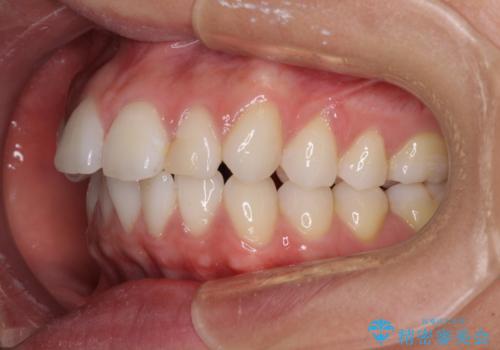

- くちばしのような前歯の突出感を気にして来院された患者様です。

上下左右第一小臼歯4本を抜歯して、積極的に口元を引っ込めるよう、ワイヤー装置にて矯正治療を行うこととしました。

抜歯矯正を行ったことで、顎先のつっぱり感や口元の閉じにくさを解消することができました。